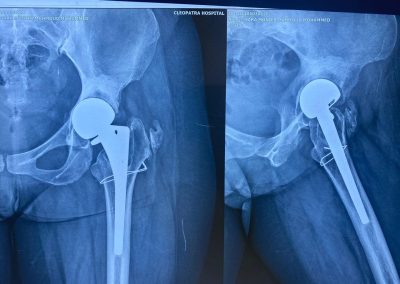

أجرت جراحة نصف مفصل بالحوض منذ ٢٠٠٦

تبين الأشعات وجود فجوات عظمية بالحق مع بروز داخلي لرأس المفصل مع وجود الام شديده.